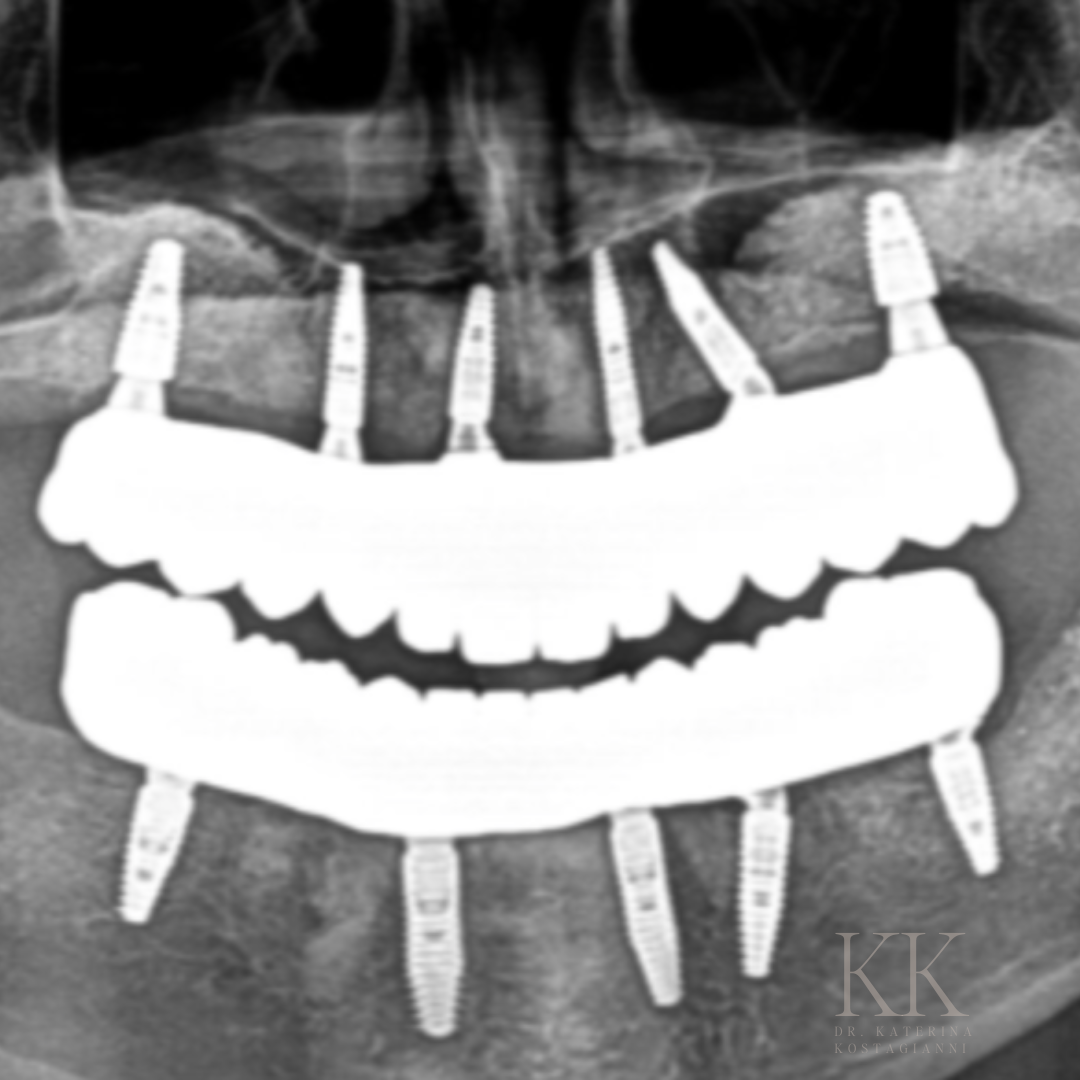

CASE STUDY 1

I had the privilege of restoring this patient’s smile using the All-on-X dental implant solution. This was a complex case that required thoughtful planning and precision. By strategically placing the implants, we ensured not only a beautiful aesthetic outcome, but more importantly, long-term function and stability. Cases like these remind me how transformative implant dentistry can be - not just for a smile, but for a patient’s confidence and quality of life.